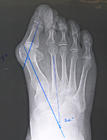

拇趾拇趾外翻的發病原因極其複雜,從臨床統計學來看由於受到生活水平、生活習慣的影響,各不同地域或不同國家,從各發病原因,發病幾年來講有所不同。一般來講,其發病原因有以下幾方面因素。一、遺傳因素;二、穿鞋因素;另外,在拇外翻的原因中,除了上述兩種最常見原因外,還有一些非常見原因,如:一、類風濕性關節炎,由於病變直接侵犯跖趾關節,造成跖趾關節變形,而形成拇外翻畸形。二、外傷因素,由於外傷造成關節、關節周圍軟組織,成骨折造成拇外翻畸形。三、神經肌肉性疾病,也可以造成拇外翻畸形。

拇趾外翻的病理及臨床表現

拇趾二、第一跖骨頭內側受長期鞋的擠壓,摩擦,局部滑囊增厚,內側骨贅增生,形成拇囊炎腫(bunion),當局部有無菌性炎症時,表現為紅、腫、疼痛,此時稱拇囊炎。

三、拇趾過度向外偏斜,而將第Ⅱ趾背起,造成第Ⅱ趾槌狀趾,仰趾畸形,當形成硬性槌狀趾時,多伴有趾間關節背側的雞眼,另外第Ⅴ趾受鞋向內側擠壓,也會形成槌狀趾畸形,而在趾間關節形成雞眼,可伴有劇烈疼痛。